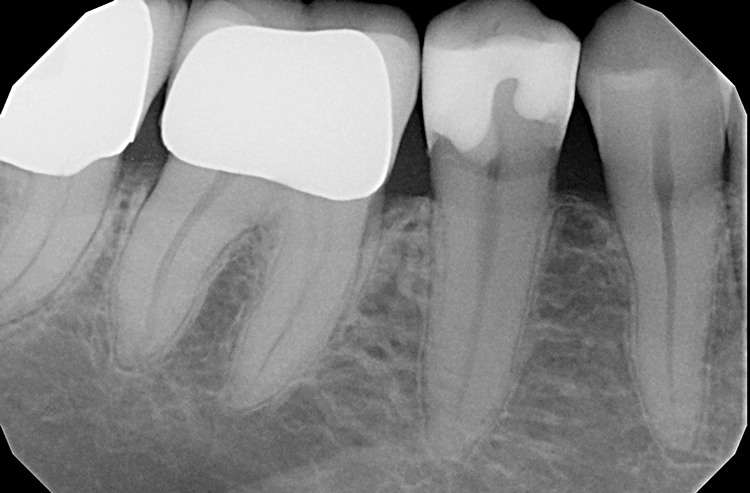

Die weitere Versorgung der Kavität erfolgte analog zu Fall 1 nach Anwendung eines klassischen Etch&Rinse-Mehrflaschenadhäsivs und schichtweiser Applikation und Polymerisation von Venus Diamond ONE (Kulzer) mit einem Hochleistungs-LED-Polymerisationsgerät > 1.000 mW/cm2 für jeweils 20 Sekunden Lediglich anstelle des Venus Diamond Flow Baseliners kam aufgrund der sehr hohen ästhetischen Ansprüche des Patienten Venus Diamond Flow in der Farbe A2 zum Einsatz – der Patient hätte keinen weiß-opaken Rand an seiner Restauration akzeptiert. Das Ergebnis (Abb. 9) überzeugte den Patienten nicht nur funktionell, sondern vorrangig ästhetisch: Auch hier passt sich die Universalfarbe perfekt an die Zahnhartsubstanz an. Zur Überprüfung der Ausdehnung der Überkappung wurde im Anschluss an die Versorgung eine Zahnfilm-Röntgenaufnahme erstellt (Abb. 10).

Das Bild zeigt den perfekten Randschluss der Restauration in Kombination aus Venus Diamond Flow A2 und Venus Diamond ONE. Beeindruckend ist zudem die sehr hohe Röntgenopazität des Materials. Das pulpanahe, weniger röntgenopake Material ist das TheraCal LC-Überkappungsmaterial.